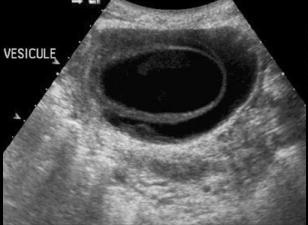

Image echographique : Image

echographique a susgestion de syndrome Mirizzi est image d'une

calcule en coince a infundibulum de la vesicule biliaire ou

intraluminal du canal hepatique commun . Une dilatation de

voie biliaire principale et et des voies biliaires

intrahepatiques en amont est souvant se presente .Et image d' une inflammation chronique de

vesicule biliaire etre en voyait

Image echographique

d'une calcul du collet vesiculaire compressee sur

le canal hepatique commune . Les voies biliaires en

amont sont dilatees . Vesicule biliaire est en

inflamee a paroi tres epais ( cholecystite chronique

) :: Syndrome de Mirizzi |